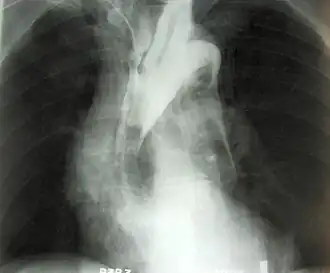

Een aneurysma (Grieks ἀνεύρυσμα, meervoud aneurysmata) is een plaatselijke verwijding van een (meestal) slagaderlijk bloedvat, als gevolg van een ter plaatse zwakke vaatwand. Het meest voorkomend is een aneurysma van de aorta, de slagader in de buik of het abdomen. Men spreekt in dat geval van een abdominaal aorta-aneurysma (AAA). Een aneurysma van de aorta ter hoogte van de borstkas, is een thoracaal aorta-aneurysma (TAA). Een aneurysma gaat meestal niet gepaard met klachten.

Symptomen

Diagnose (opsporing) en behandeling van een AAA

Vanwege het levensbedreigende karakter, is het aan te raden een verdenking op een aneurysma goed te laten onderzoeken. Lichamelijk onderzoek alleen sluit een aneurysma nooit uit. Als gouden standaard voor het aantonen van een aneurysma wordt een echografie van de buik gebruikt. Hierbij kan men nauwkeurig de juiste diameter van het verwijde bloedvat bepalen. Hierbij houdt men de grootst te meten voor-achterwaartse diameter, de Anterior-Posterior- of AP-diameter, aan. Als arbitraire grens wordt een diameter van 55 mm gebruikt bij mannen en 50 mm bij vrouwen. Uit onderzoek is gebleken dat vanaf deze diameter het risico op een vaatbreuk of ruptuur reëel is, en de risico's van een operatie niet meer opwegen tegen het risico op scheuren.

Een CT-scan met contrastvloeistof laat precies zien hoe de vaatboom rond de aorta eruitziet. Dit bepaalt ook of men laparo-tomisch, via het openen van de buikholte, of endovasculair (vanuit de vaten na benadering in de liesslagader(s)) opereert. Men kiest respectievelijk voor het inhechten van een aortabifurcatieprothese, ook wel broekprothese genoemd, of een endovasculaire stent op maat. Laatstgenoemde procedure staat bekend als EVAR; Endovascular Aneurysm Repair.